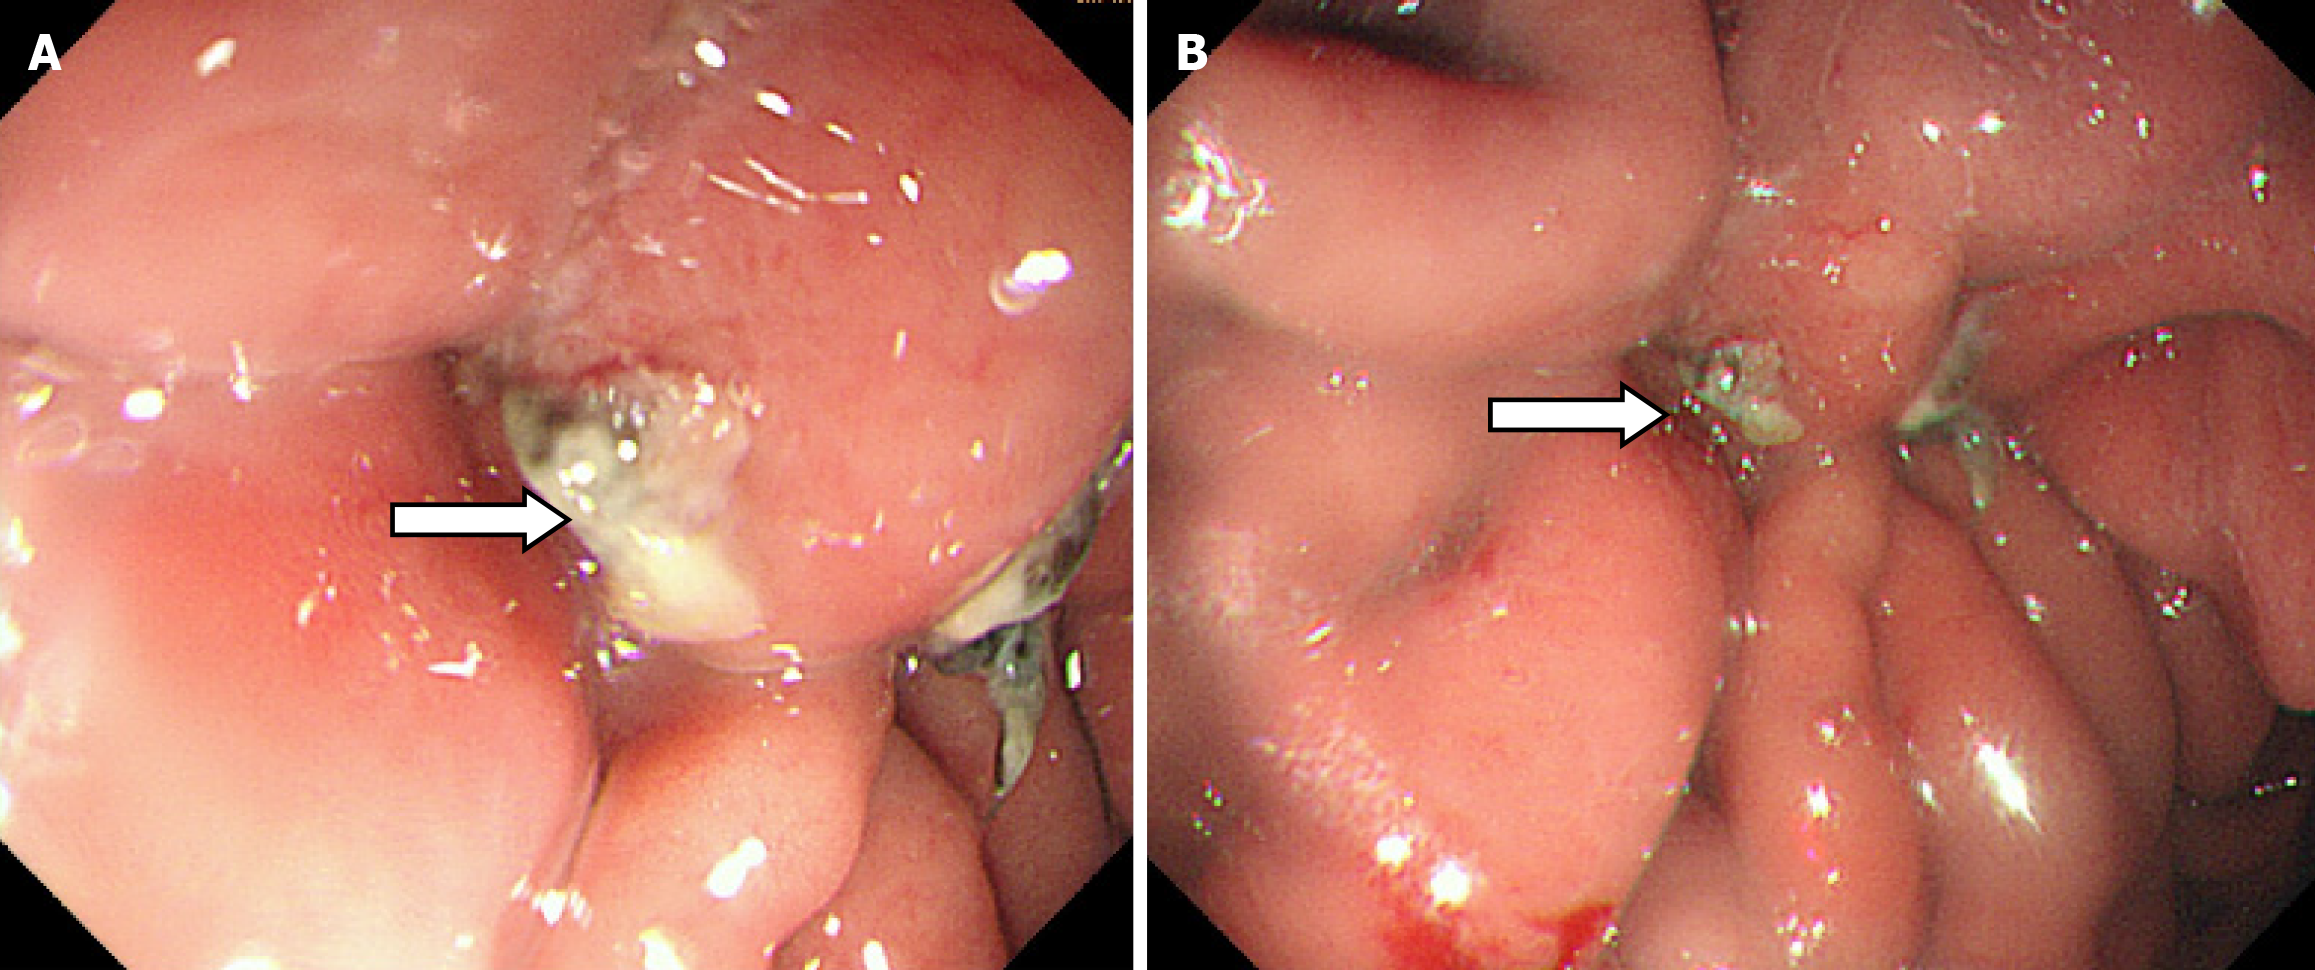

During the postoperative fasting period, we consulted with a nutritionist again. The energy and nitrogen sources were supplied according to the patient's disease status until he returned to a roughly normal diet and then changed to oral enteral nutrition. Drainage tubes of smaller diameter were placed successively and then removed. Reexamination by abdominal CT confirmed that the thoracoabdominal wall swelling had improved (Figure 5), gastric endoscopy verified gastric ulcer improvement and the gastric fistula was not observed at this time (Figure 6). The patient’s clinical symptoms, especially pain, were alleviated. Pathological examination of the sinus showed fibrous and inflammatory granulation tissue with a giant cell reaction. His condition improved and he was again discharged on June 17, 2020.